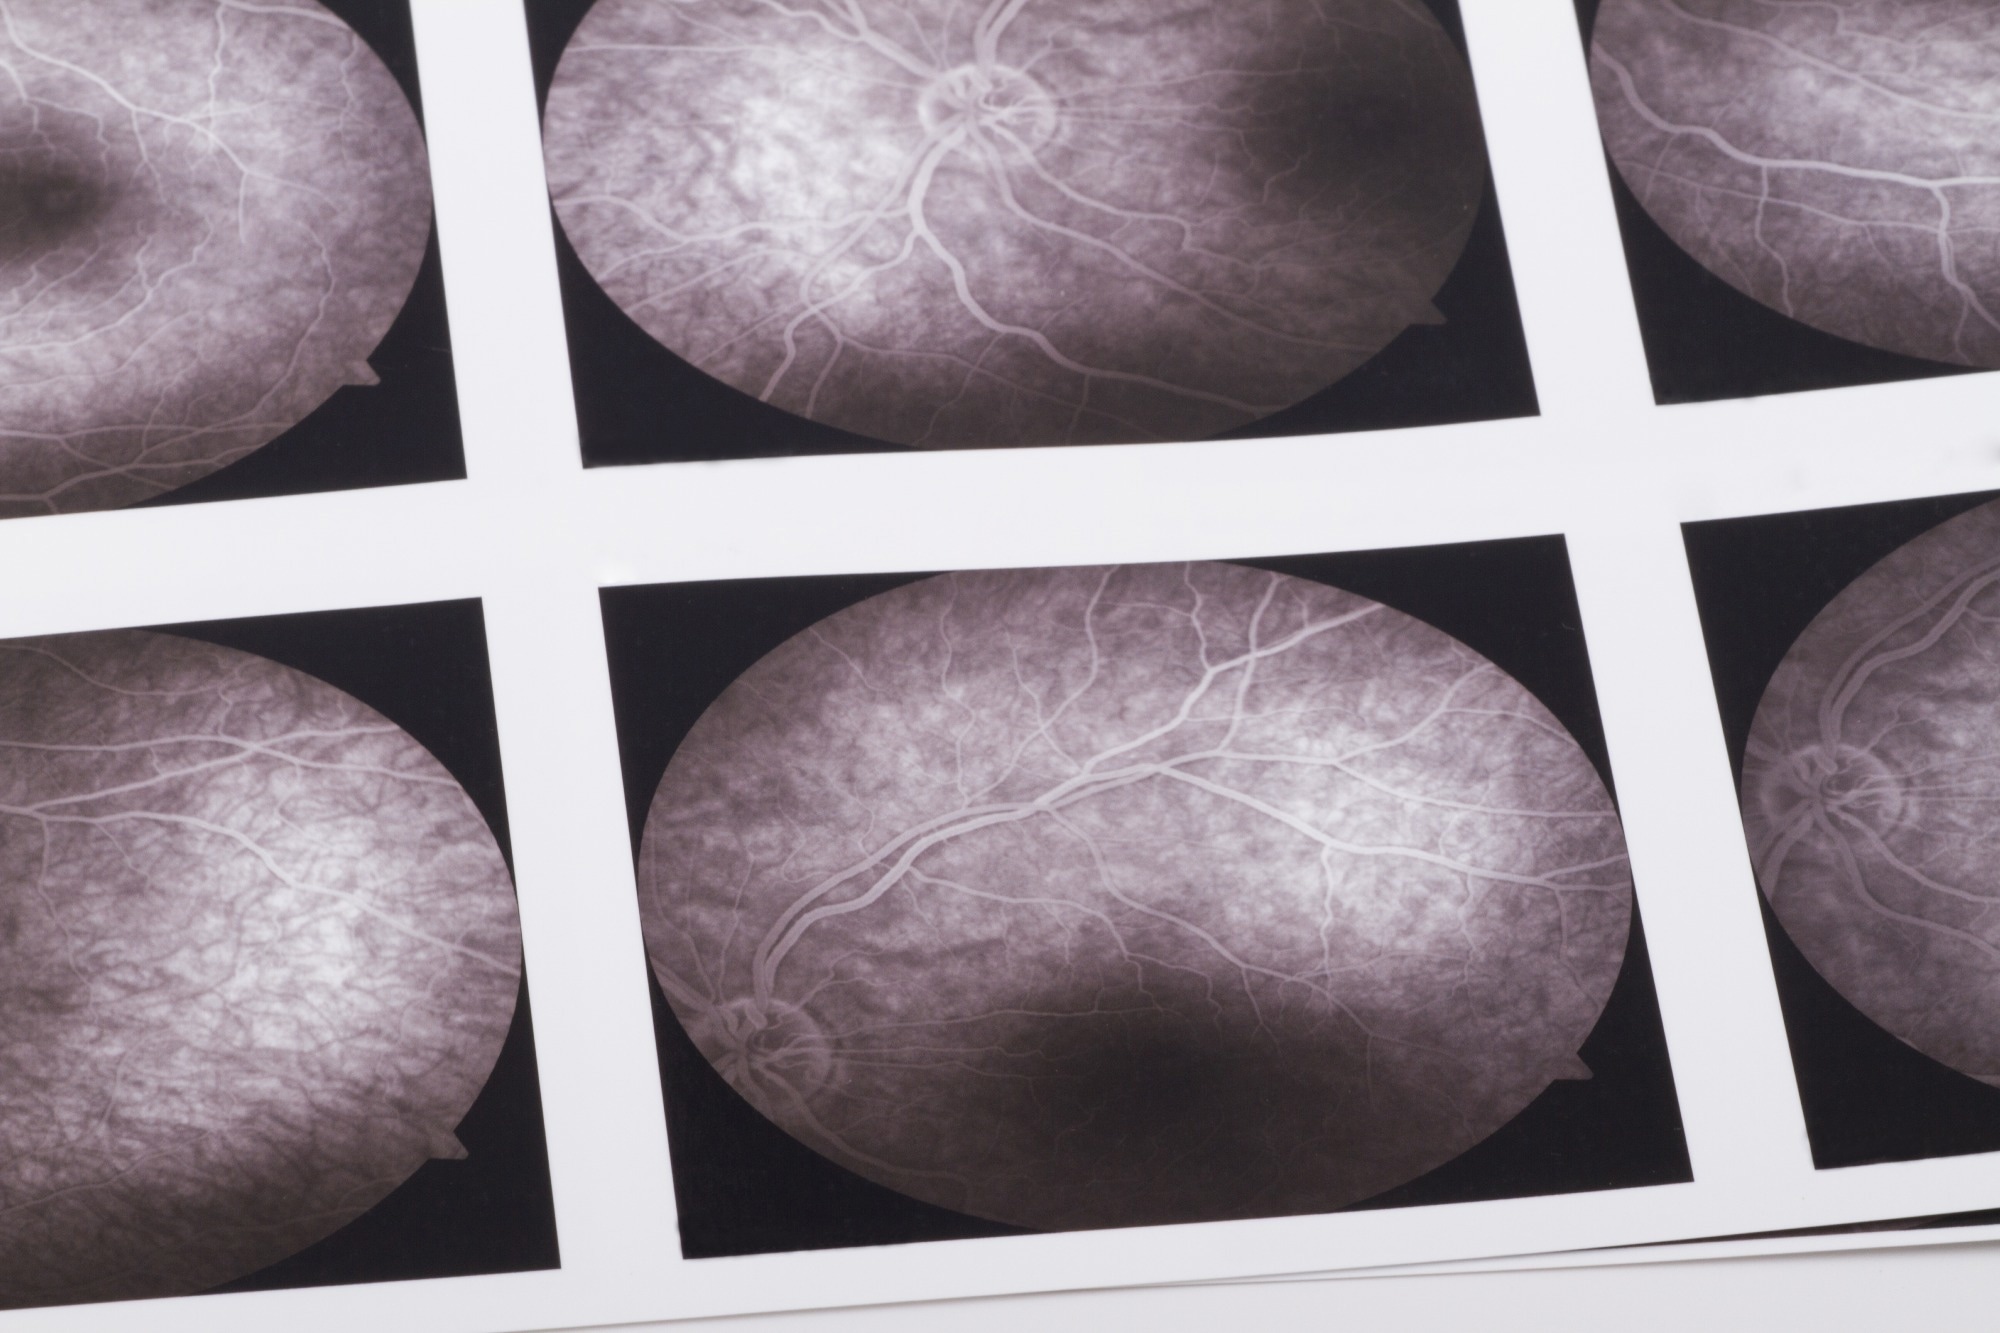

Study: Early detection of dementia through retinal imaging and trustworthy AI. Image Credit: bfk / ShutterstockStudy: Early detection of dementia through retinal imaging and trustworthy AI. Image Credit: bfk / Shutterstock

OCTA is a state-of-the-art imaging technique that allows for rapid and noninvasive imaging of the retinal microvasculature, including even the smallest capillaries with a resolution of 5–6μm. This technology provides detailed insights into the microvascular network and the structure of the foveal avascular zone across different retinal layers, as well as the choroid.

In this study, the researchers developed and tested a novel deep-learning model called "Eye-AD." The model was specifically designed to analyze OCTA images and identify patients with early-onset Alzheimer’s disease or mild cognitive impairment. The model processes high-resolution data from various retinal layers, including the superficial vascular complex (SVC), deep vascular complex (DVC), and choriocapillaris (CC), to detect patterns associated with cognitive decline.

The study data was collected from two primary cohorts—ROMCI (Retinal OCTA-based MCI detection) and ROAD (Retinal OCTA-based EOAD detection)—which comprised retinal images centered on the fovea. The images captured information on the retina's vascular structures, providing the dataset for model training and evaluation.